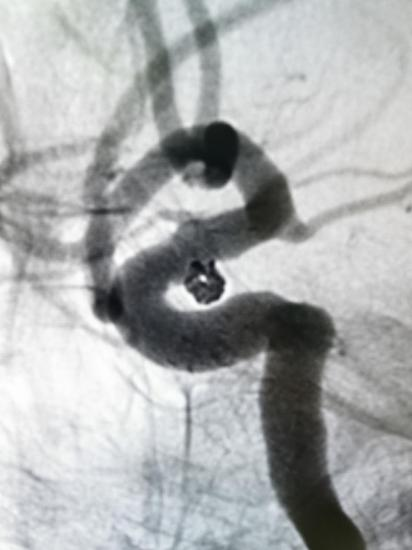

4.入路血管损伤

术中栓塞:

此患者动脉瘤栓塞术后一般情况良好,自诉眼睑下垂明显改善,临床随访中。